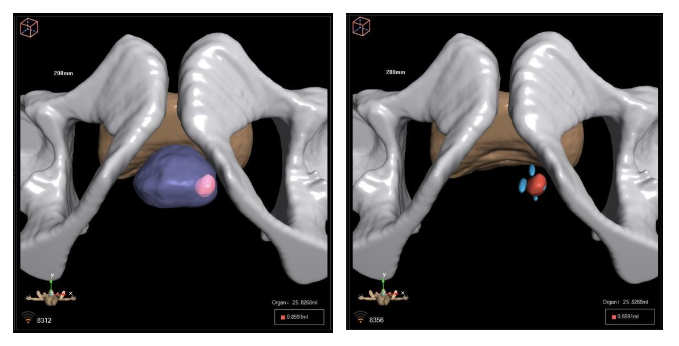

患者术前MR与病理信息

术前依据前列腺MRI结果精准定位病灶